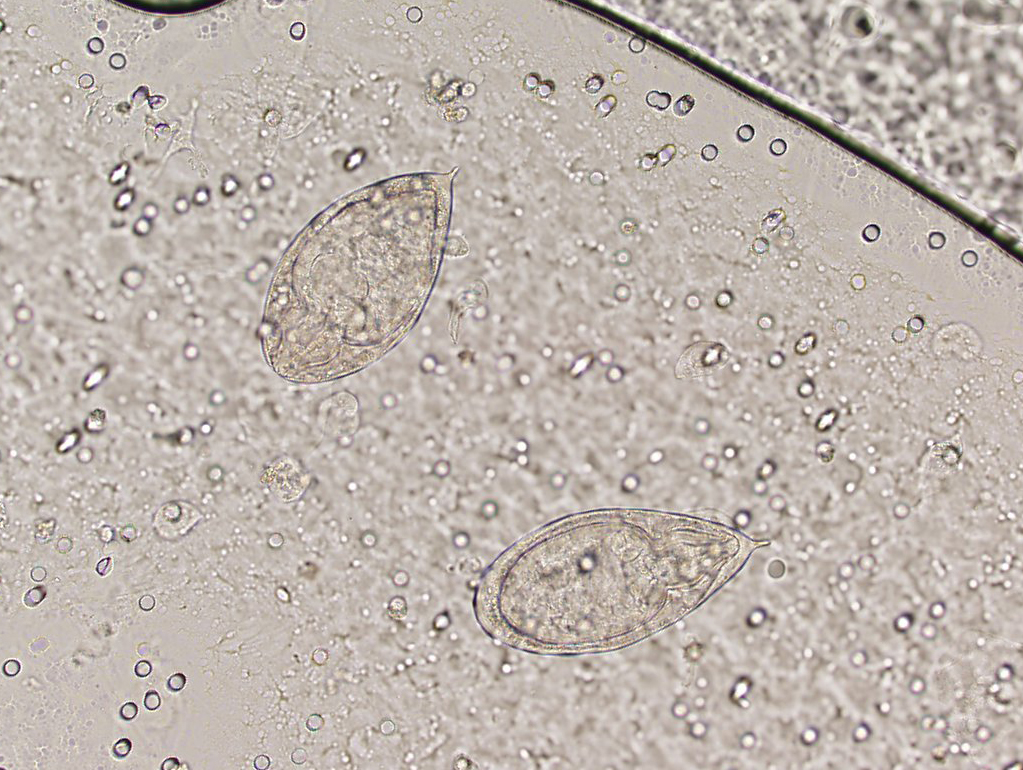

JoF Free FullText Urine Sediment Findings and the Immune Response Black Bugs Coming Out Of Urine Peeing tiny black bugs can be a symptom of an underlying health issue. Possible causes include urinary tract infections, kidney stones, bladder. Parasites in the urine may be a sign of urinary tract infection (uti) like schistosomiasis or male or female infection of. Whether you have black pepper flakes in urine during pregnancy or due to other complications in the. Black Bugs Coming Out Of Urine.

Trichomonas In Urine Black Bugs Coming Out Of Urine Parasites in the urine may be a sign of urinary tract infection (uti) like schistosomiasis or male or female infection of. When you notice little black specks in urine, you should inform your doctor about the symptoms, even if you do not experience any pain or discomfort. Whether you have black pepper flakes in urine during pregnancy or due to. Black Bugs Coming Out Of Urine.